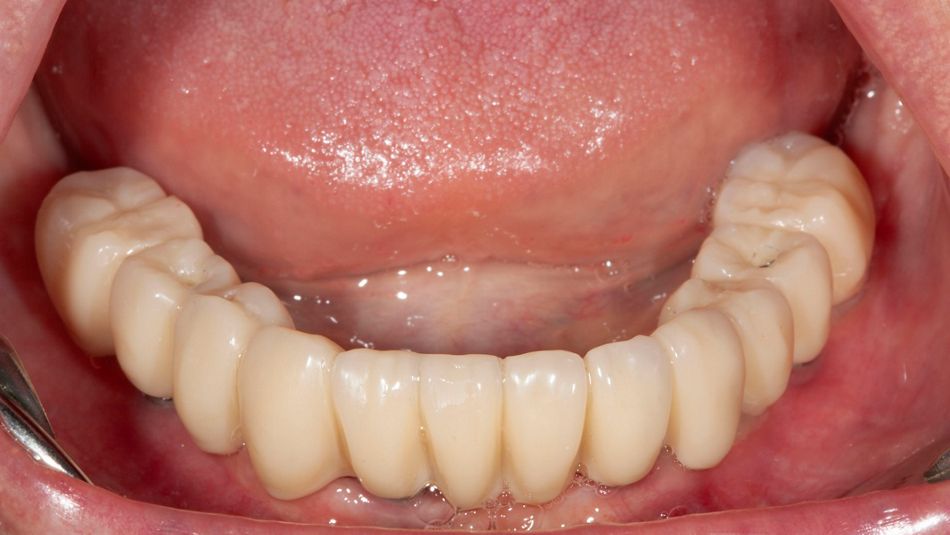

16. Display of the finished lower jaw work after osseointegration.